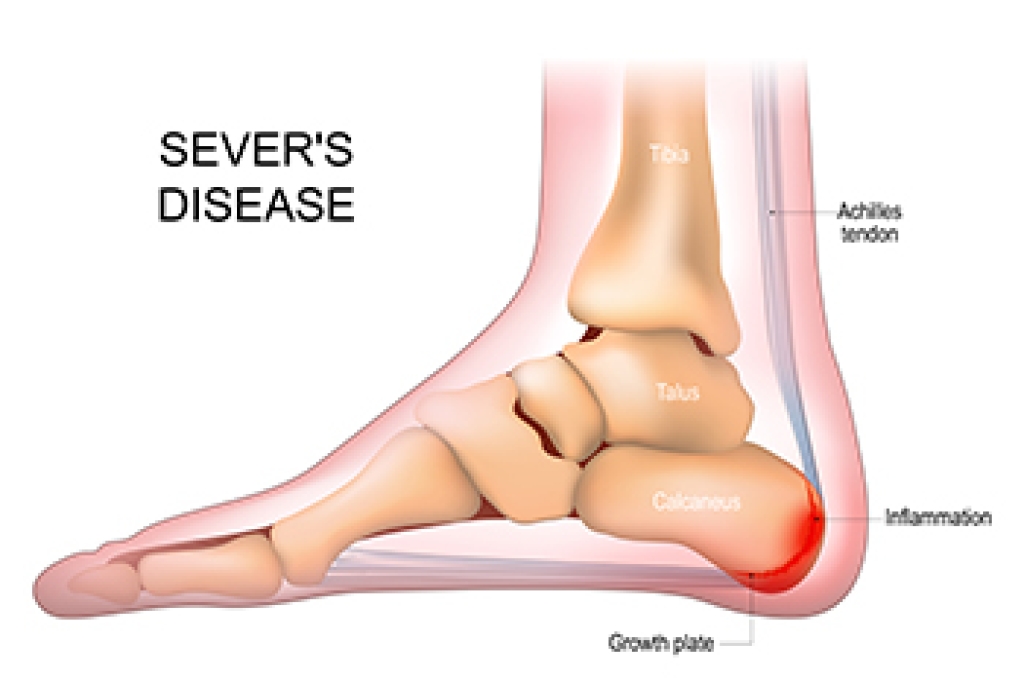

What Is Sever’s Disease?

Sever's disease, also known as calcaneal apophysitis, is a common cause of heel pain in growing children, particularly those who are active in sports. This condition occurs when the growth plate at the back of the heel becomes irritated due to repetitive stress or overuse. It is often seen in children between the ages of eight and 14, especially those who participate in activities that involve running or jumping. Symptoms of Sever's disease include pain, tenderness, and swelling at the back of the heel, which may worsen during or after physical activity. Management of this condition typically involves rest and elevation to reduce inflammation. Stretching and strengthening exercises for the Achilles tendon and calf muscles can also help to relieve symptoms, and wearing cushioned shoes or using orthotic insoles may provide additional comfort. If your active child has heel pain, it is suggested that you consult a podiatrist who can accurately diagnose and treat Sever’s disease.

Sever’s Disease

Sever’s disease is also known as calcaneal apophysitis, which is a medical condition that causes heel pain I none or both feet. The disease is known to affect children between the ages of 8 and 14.

Sever’s disease occurs when part of the child’s heel known as the growth plate (calcaneal epiphysis) is attached to the Achilles tendon. This area can suffer injury when the muscles and tendons of the growing foot do not keep pace with bone growth. Therefore, the constant pain which one experiences at the back of the heel will make the child unable to put any weight on the heel. The child is then forced to walk on their toes.

Acute pain – Pain associated with Sever’s disease is usually felt in the heel when the child engages in physical activity such as walking, jumping and or running.

Highly active – Children who are very active are among the most susceptible in experiencing Sever’s disease, because of the stress and tension placed on their feet.